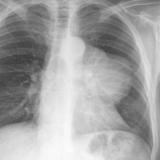

Case 8a Thymoma PA

Date: 03/27/2009

Views: 9539